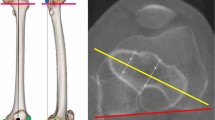

Sixteen randomly chosen dried cadaveric femora were used; all of which were obtained via approved anatomical body donation programmes. The protocol complied with the Human Research Act and the guidelines of the Swiss Association of Research Ethics Committees. Institutional review boards of both Lerdsin Hospital and the Lucerne Cantonal Hospital approved the experimental protocol. Informed consent was obtained from the cadaver donors or their next-of-kin by anatomical institues in Thailand and the Netherlands, respectively. Eight femora were obtained from an Asian and eight from a Caucasian population. All bones were confirmed to be free of any history of lower extremity trauma or disease. The examination setup was standardized by positioning the bones in a neutral position which will be defined later in the text. A Kirschner wire was inserted into the tip of the GT, which we defined as the intersection between the line connecting the centre of the femoral head to the centre of the femoral neck on an axial view and the most proximal aspect along the greater trochanteric crest on the ap view (Fig. 1). This intersection was chosen as the greater trochanter is typically a massif with multiple tips rather than a structure with one single tip. Depending on the angle chosen for the ap beam path when visualising the proximal femur different tips may be interpreted as the true tip of the GT. In the axial view the nail entry point should ideally lie in the plan connecting the center of the femoral head and neck to allow for optimal positioning of the cephalic device, irrespective of the chosen implant. Therefore, defining the most proximal aspect of the trochanteric crest in the ap view that corresponds with an optimal axial positioning of the entry point should be beneficial.

Marking the anatomical landmarks. A wire was inserted into the tip of greater trochanter, which was defined as the intersection between the line connecting the centre of the femoral head with the centre of the femoral neck on axial view and the most proximal aspect along the greater trochanteric crest on the anteroposterior view. The blue lines are markers attached to the antero- and postero-superior borders of the greater trochanter.

A radiopaque marker was attached to the antero-superior and postero-superior border of the greater trochanter to identify the profile of the greater trochanter in the images obtained by C-arm.

In the following step, the neutral position of the femur was determined. The C-arm was positioned in the lateral projection with the beam parallel to the ground and perpendicular to the femoral condyles to obtain a lateral view of the distal femur. The bone was manipulated until the posterior femoral condyles overlapped perfectly and were parallel to the floor. The femur was fixed in this position. The C-arm was then moved proximally parallel to the bone and rotated to the ap projection of the proximal femur (Fig. 2). The C-arm was gradually rotated in 5° intervals from 30° internal to 30° external rotation (Fig. 3). Images of the different viewing angles were saved. Positive viewing angles represent internal rotation, negative viewing angles correspond to external rotation of the femur.

Positioning of the femur and c-arm. Lateral position of the c-arm to determine the neutral position of the femur with perfectly overlapping femoral condyles. The c-arm was moved proximally and into a vertical projection. It was then gradually rotated while obtaining images in 5° intervals from 30° internal rotation to 30° external rotation.

Digital measurements were performed using ImageJ software (ImageJ v1.49, National Institutes of Health, USA). The distance between the cortical overlap line and the tip of the GT (Fig. 5), the distance between the posterior border of the GT to the tip of the GT in the various views and the antetorsion of the proximal femur (defined in the axial plane as the angle between the line defined by the posterior aspect of the distal femoral condyles and a line drawn from the centre of the femoral head to the midline of the femoral neck)15 were measured. The type of greater trochanteric overhang according to Grechenig et al. was evaluated in the axial radiograph16: group 1, with full access to the entry point; group 2, where the outline of the spine is projected laterally; group 3, where the entry point is partially covered and group 4, where the entry point is completely covered. The length of the femur was defined as the distance in millimetres from the tip of the GT to the most distal part of the lateral femoral condyle.